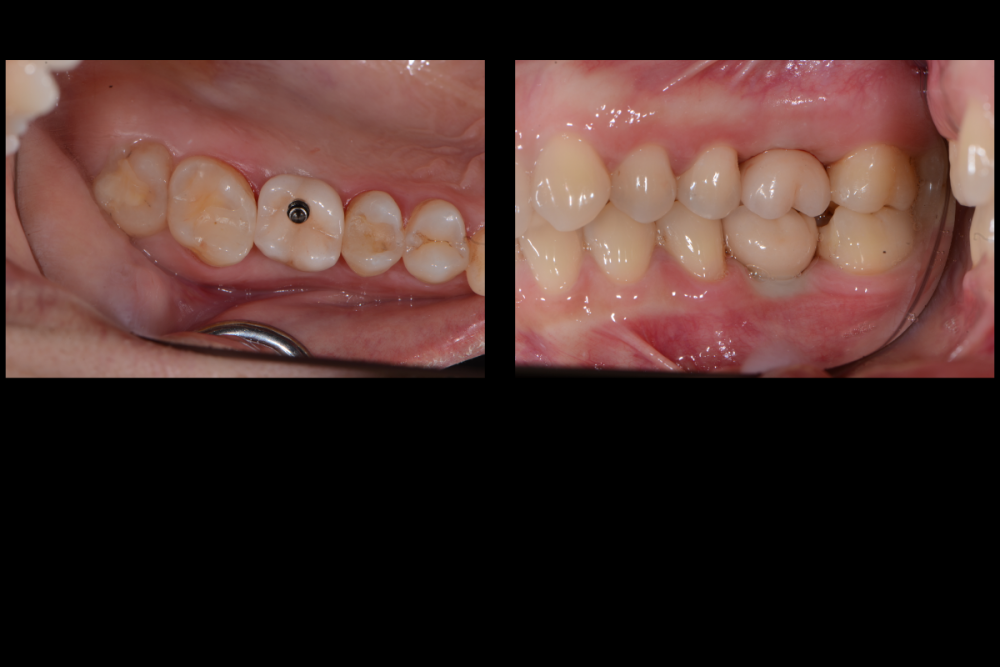

Карен Аванесов Опубликовано 10 ноября, 2021 Автор Поделиться Опубликовано 10 ноября, 2021 Придерживаясь правил форума, второе сообщение содержащее фотоматериал выдержанно в лучших традициях русской словестности, без сквернословия и непонятных иностранных слов, без применения шовного материала, широких формирователей десневой манжеты, без мягкотканной и прочей аугментации (наращивание костей что то все же не звучит прилично)), а самое главное, время затраченное на всю операцию 60 минут (имплантаты на нижней челюсти установил по лазерной технологии, без разрезов, Лазер - сила!). Время ожидания до ортопедического этапа 3 месяца. 6 1 Ссылка на комментарий